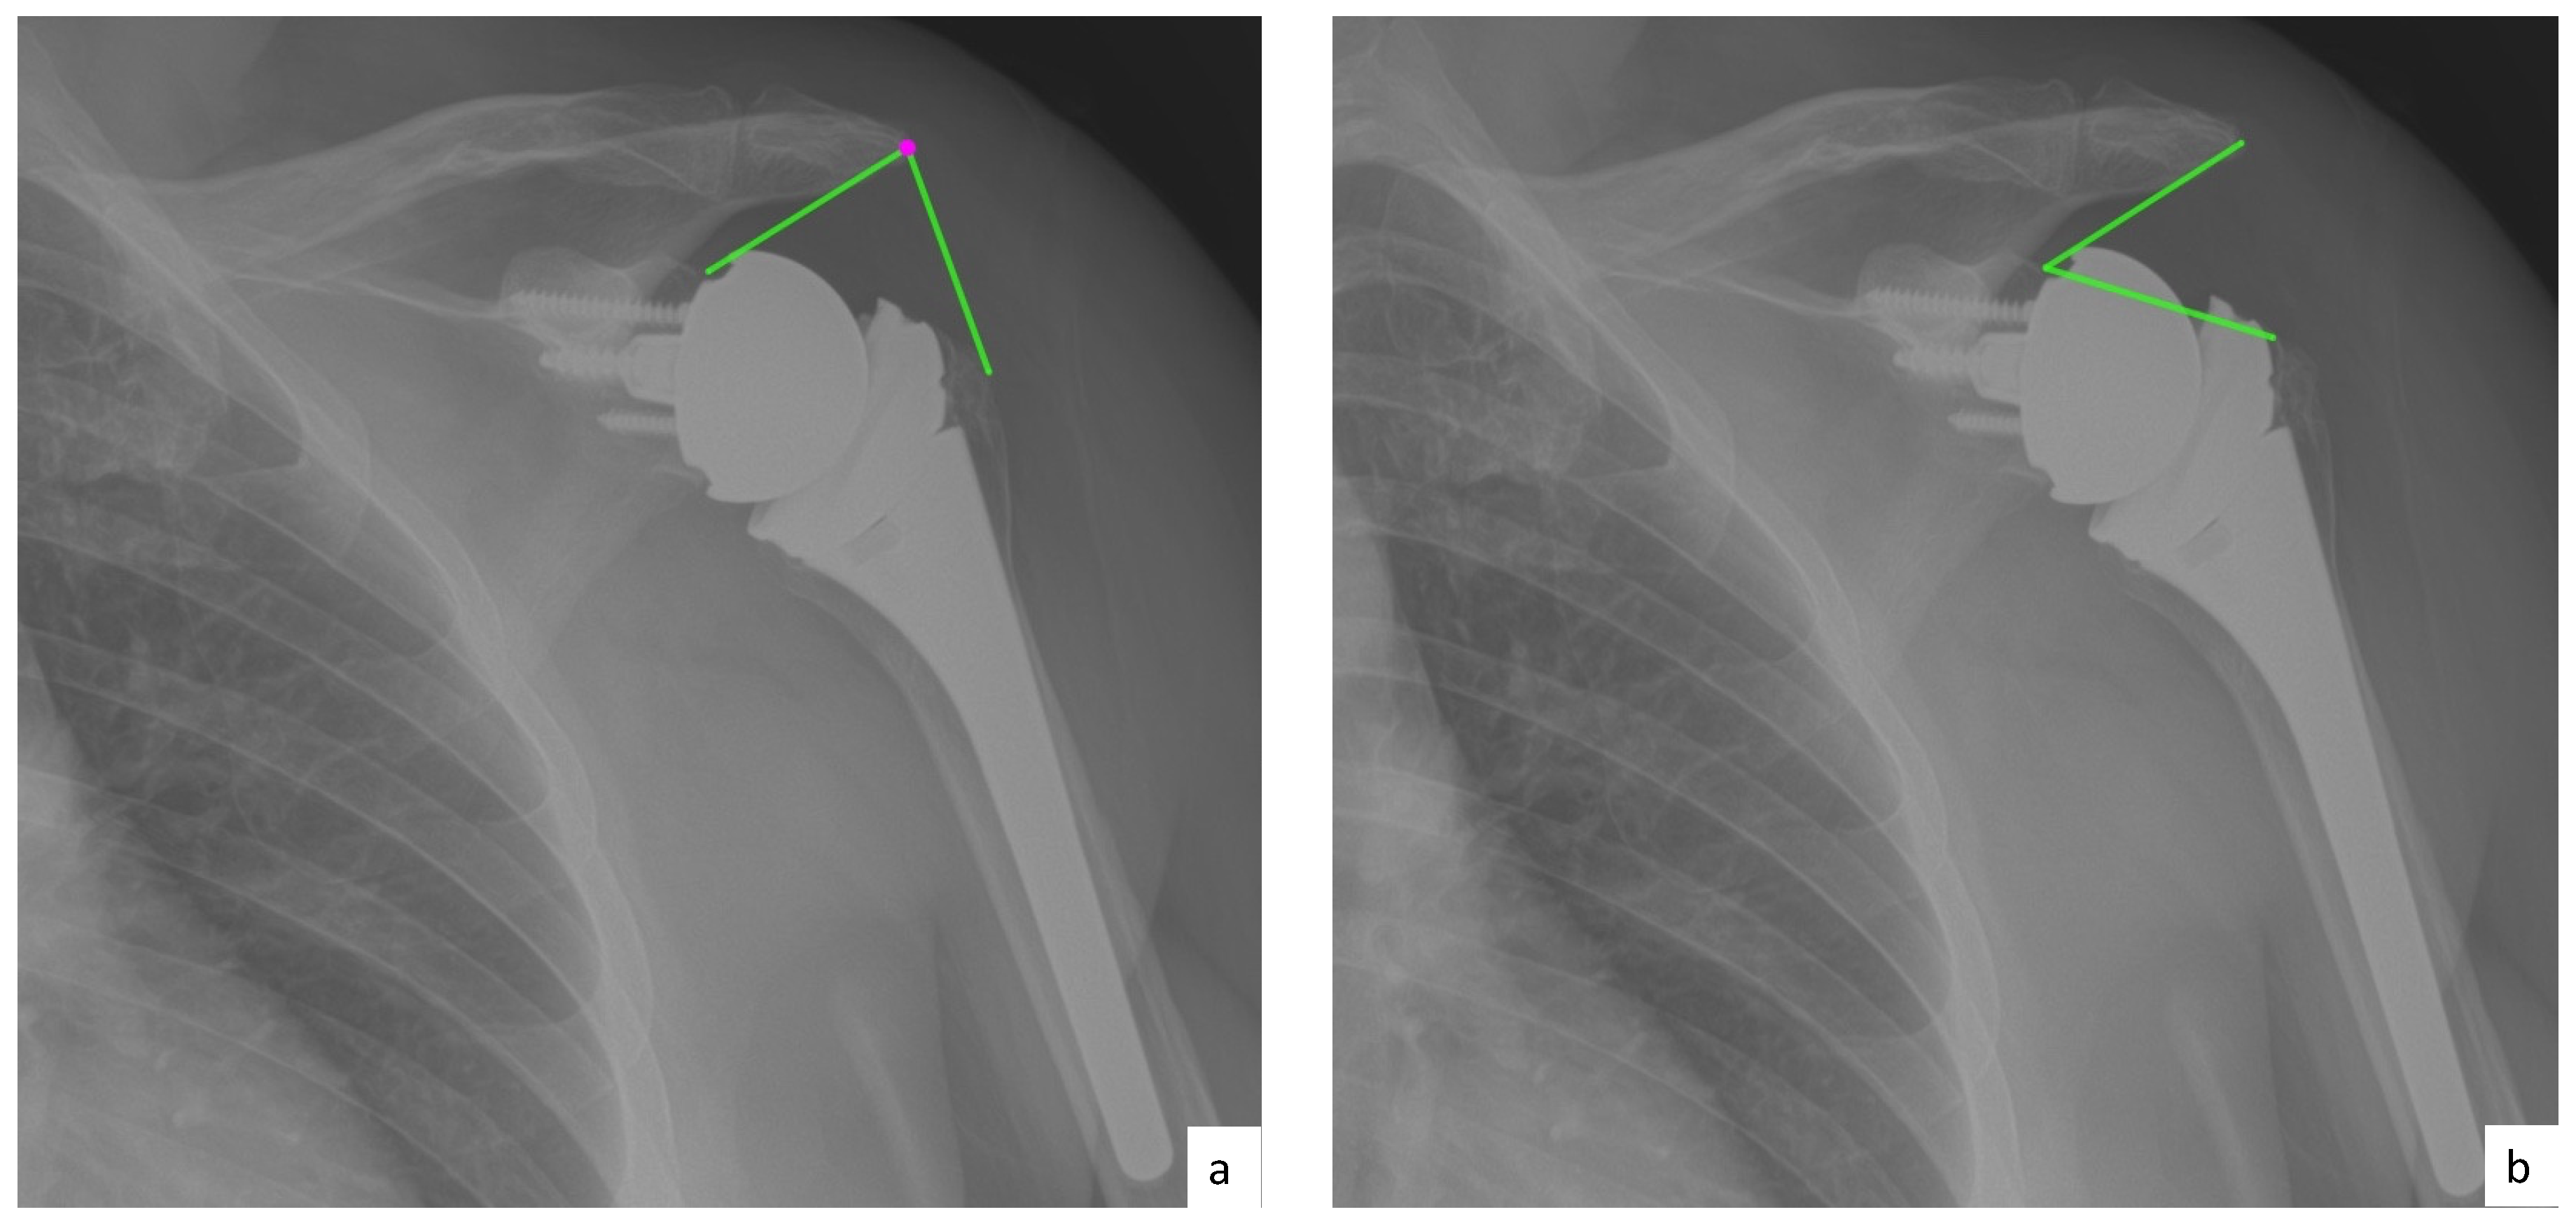

AHD was measured by calculating the perpendicular distance between the most lateral portion of the undersurface of the acromion and a line parallel to the superior border of the greater tuberosity [21] (Figure 1). LHO was measured by determining the distance from the AHD line to the most lateral projection of the greater tuberosity [21] (Figure 2). LSA was measured by drawing a line from the superior glenoid tubercle to the most lateral border of the acromion and a second line from the most lateral border of the acromion to the most lateral border of the greater tuberosity. The angle between these two lines formed the LSA [20] (Figure 3a). DSA was measured by drawing a line between the most lateral border of the acromion and the superior glenoid tubercle and drawing a second line to connect the superior glenoid tubercle with the most superior border of the greater tuberosity. The angle between these two lines formed the DSA [20] (Figure 3b). Glenoid and baseplate were determined as the angle between the floor of the supraspinatus fossa and the glenoid fossa [25] (Figure 4). COR was measured by determining the best fit circle flush to the articular surface, identifying the center of the circle in the humeral head, and then measuring the distance of the perpendicular line between the center of the humeral head and the midpoint of the line connecting the superior and inferior glenoid tubercles [24] (Figure 5b). CSA was measured by a line from the superior pole to the inferior pole of the glenoid and a line from the inferior pole to the lateral edge of the acromion [26] (Figure 5a). In addition, scapular notching was graded according to the Nerot–Sirveaux classification and severity of preoperative cuff tear arthropathy was evaluated according to the Hamada classification [27,28].

Figure 3.

(a) Lateralization shoulder angle (LSA); (b) distalization shoulder angle (DSA).